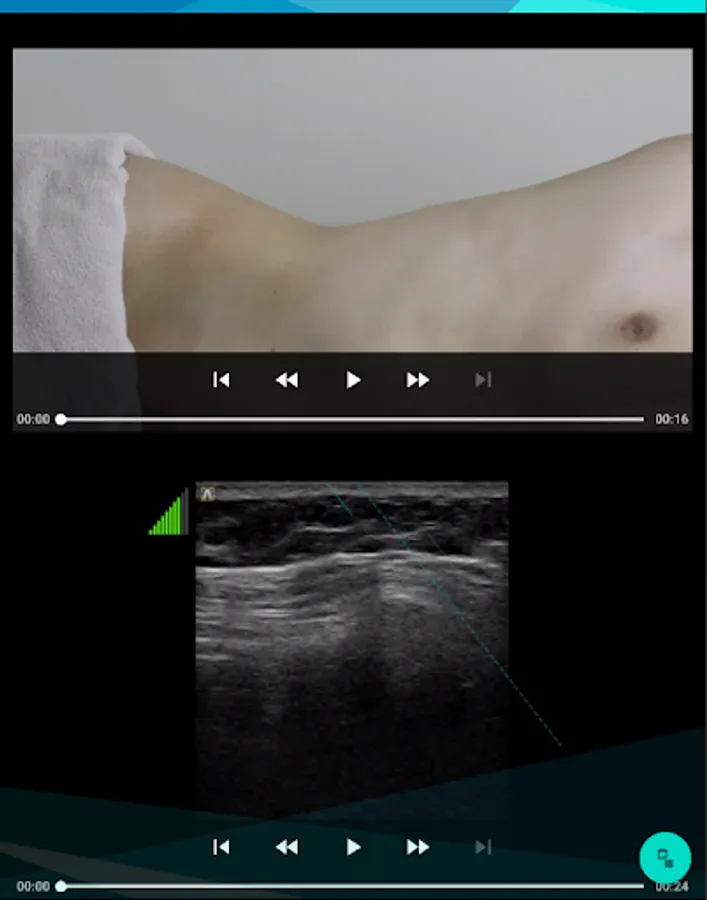

▶ Organized so that you can easily follow how to find acupuncture points and insert needles through 'ultrasound image'